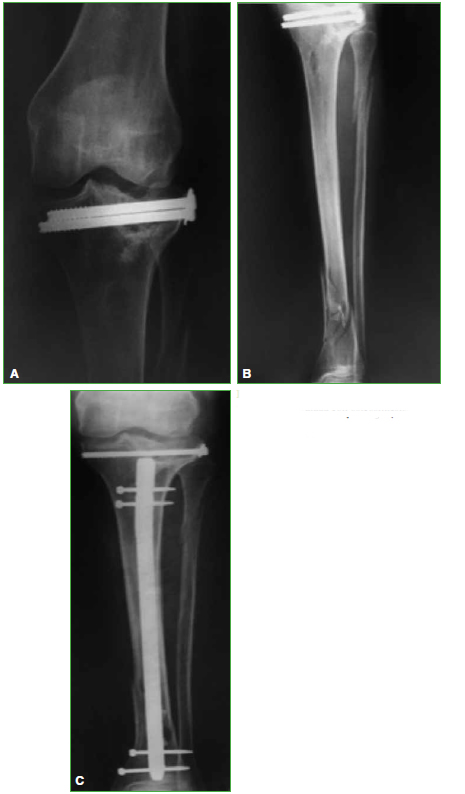

Artroplastia total de rodilla en pacientes con secuela de fracturas articulares. Resultados del seguimiento a mediano plazo

Acceso mediante suscripción PDF Acceso mediante suscripción PDF_EN (English) Acceso mediante suscripción HTML Acceso mediante suscripción Figura 1 (a-c) Acceso mediante suscripción Figura 1 (d-e) Acceso mediante suscripción Figura 1 (f) Acceso mediante suscripción Tabla 1 Acceso mediante suscripción Tabla 2 Acceso mediante suscripción Tabla 3 Acceso mediante suscripción Tabla 4